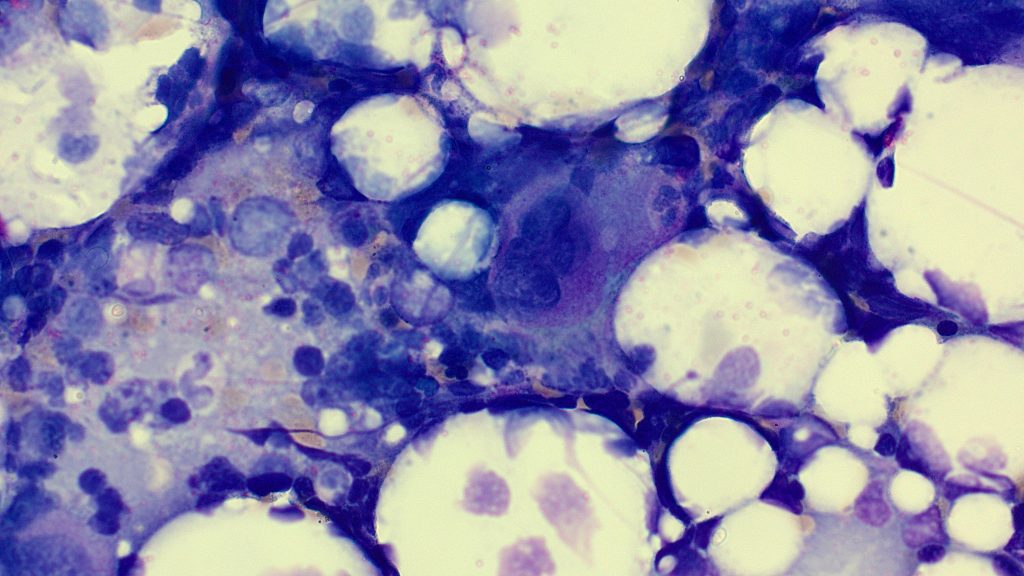

Megakaryocytes

Abnormal cytoplasm

Micromegakaryocytes

Separated nuclei

Hypolobated nuclei